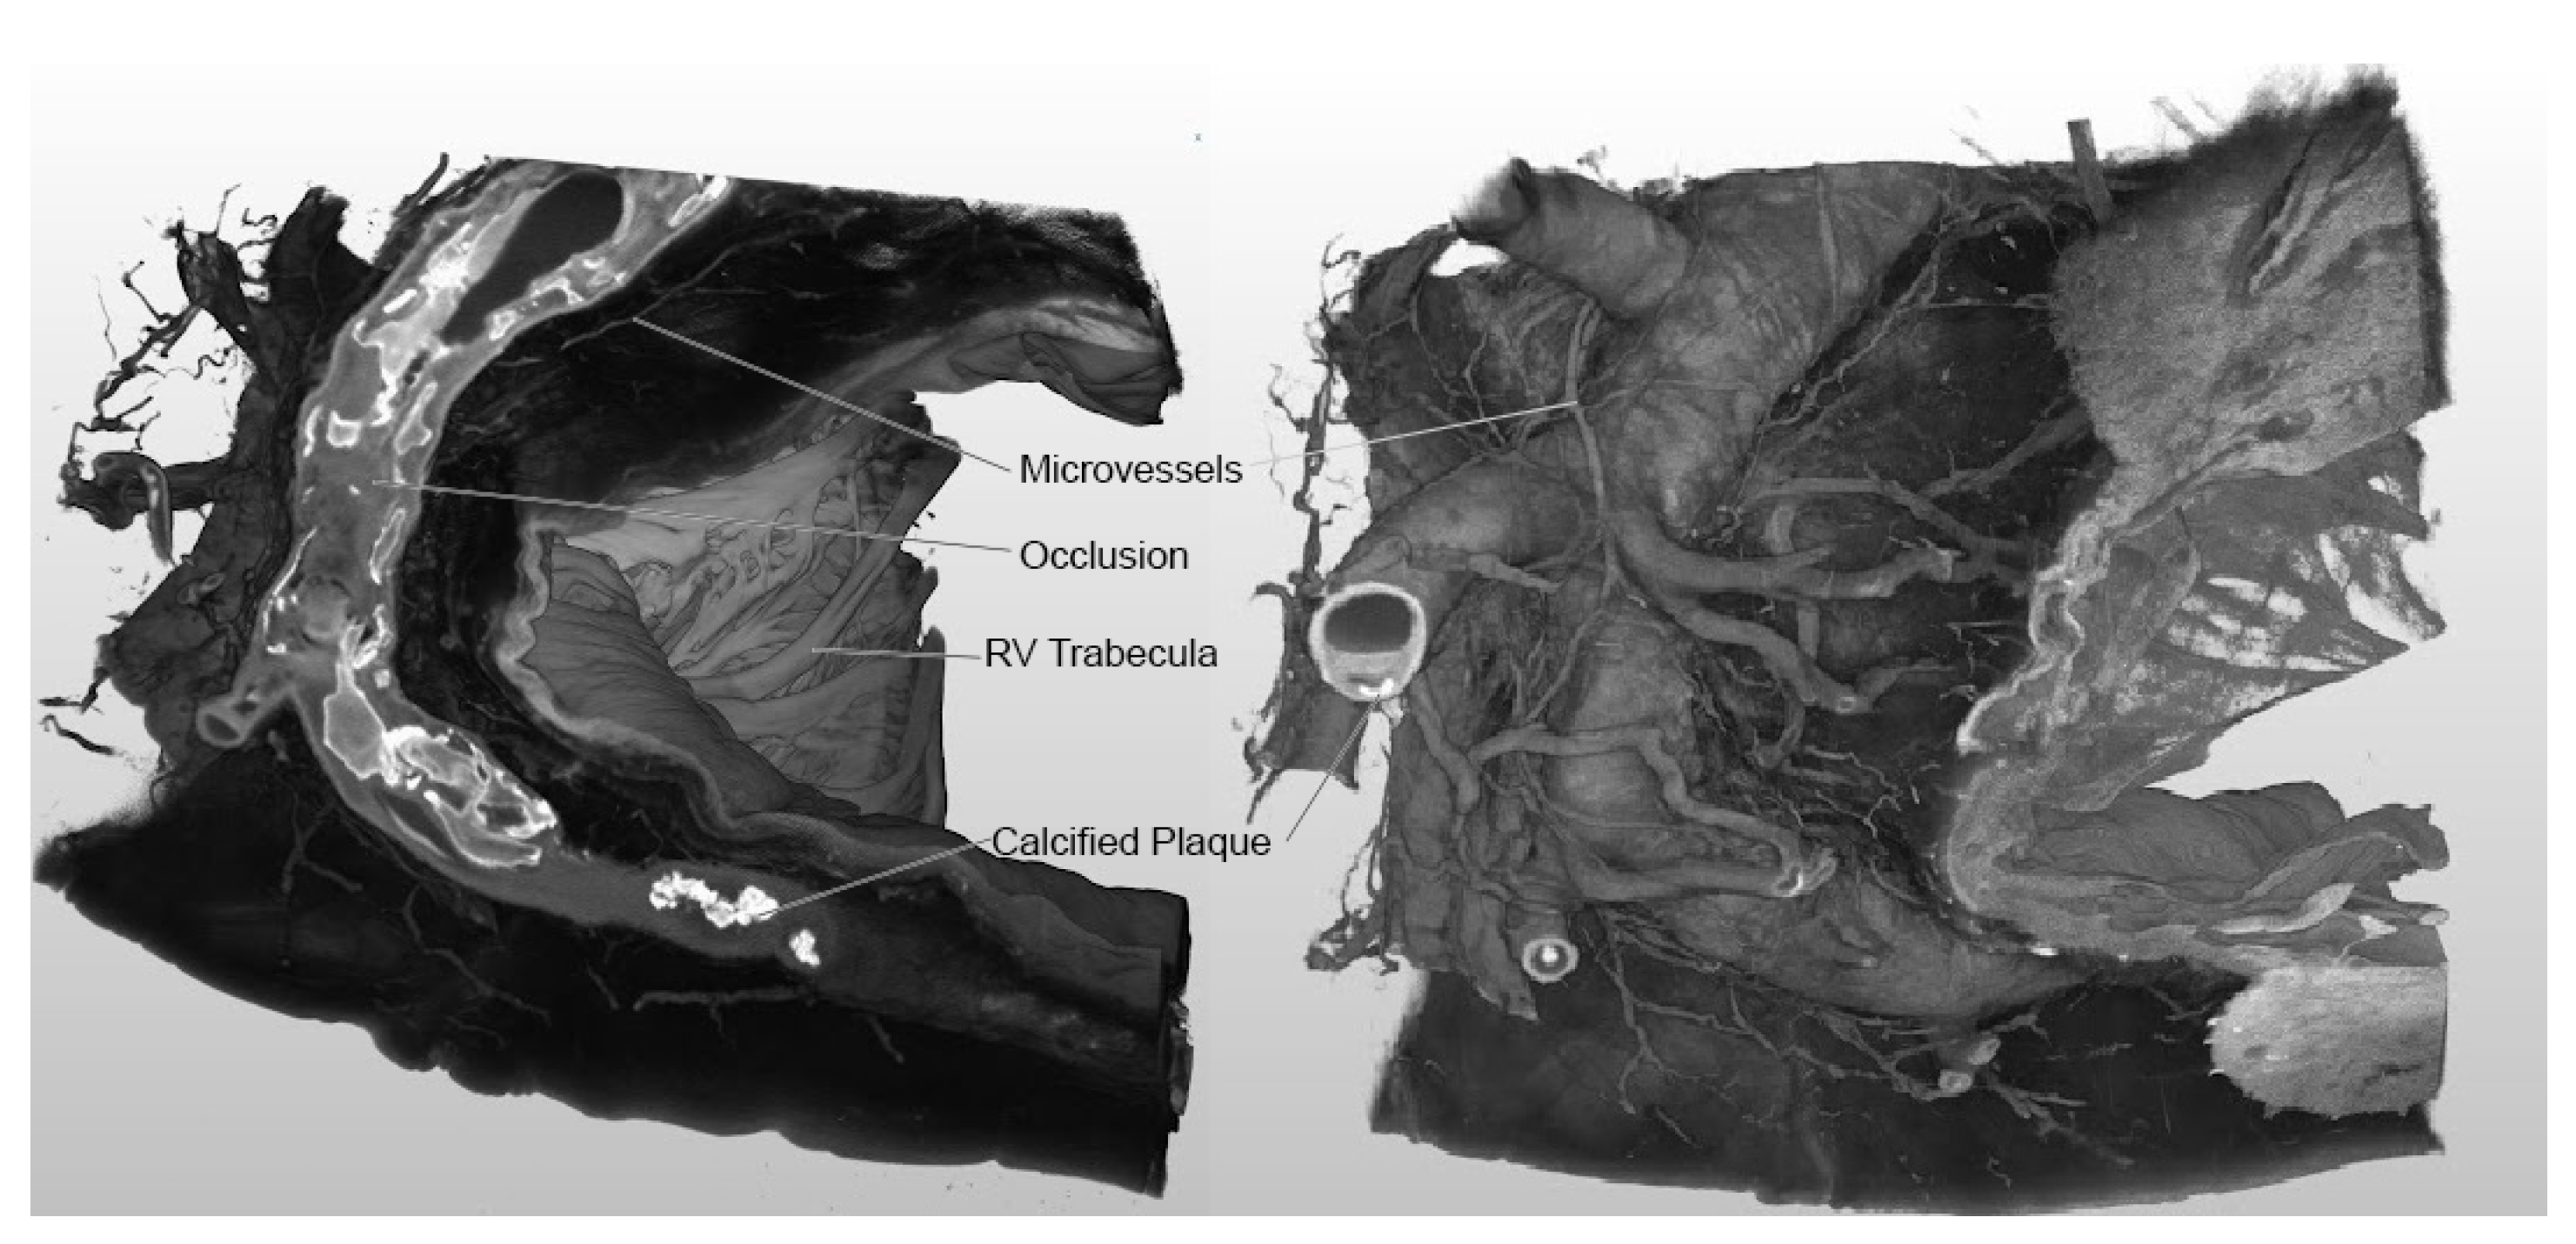

3.1. Imaging Outcomes